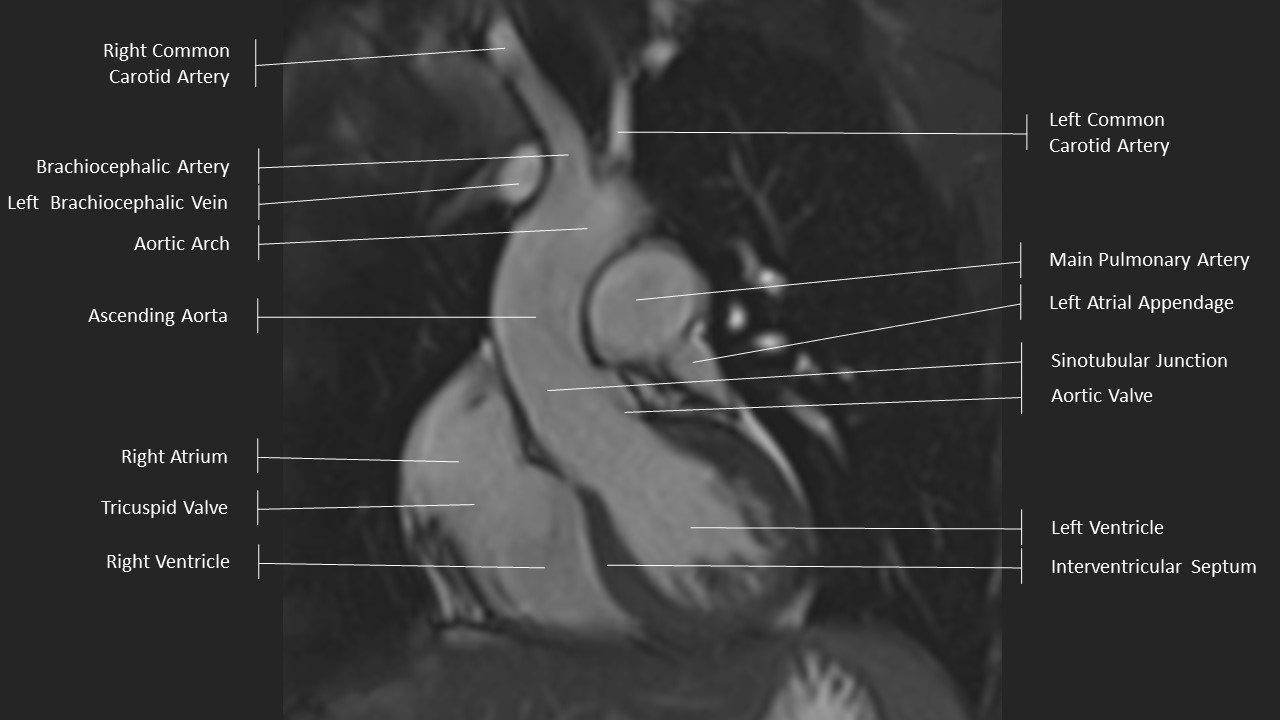

Left Ventricular Outflow Tract (LVOT) View

LVOT View